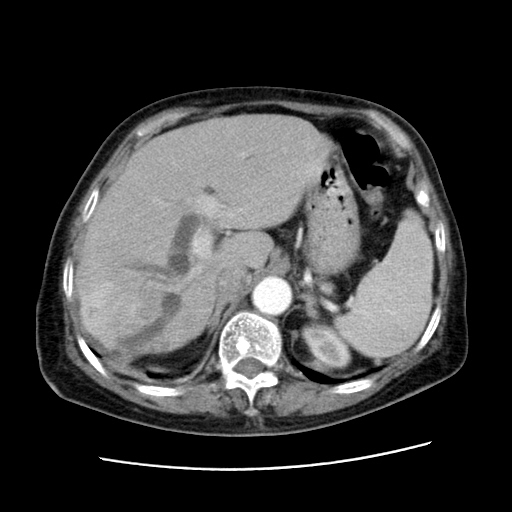

女,77.无不适

胆管扩张,壶腹部占位?

肝内胆管扩张,胆囊炎,胆囊窝积液。 右侧胸腔少量积液。

肝脏变异

肝脏变异、异位胆囊,肝右叶肝内胆管结石并肝内胆管扩张。

考虑胆管癌

本人考虑胆管细胞癌

肝右叶肝内胆管结石并肝内胆管扩张。胆总管下段梗阻,考虑壶腹部占位。